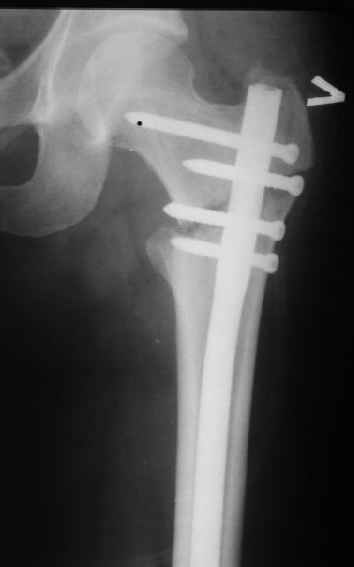

При межвертельных переломах с цефаломедуллярными гвоздями бывает, что проксимальый винт проходит или черед периферический отломок, или прямо над ним. И если остался диастаз, то этот винт при осевой нагрузке не дает сблизиться отломкам. Пример такого остеосинтеза в застарелом случае в приложении.

В качестве предупреждающей меры можно долотом разрушить латеральную стенку дистального отломка под винтом.

В частности, на проксимальном конце сделано еще одно дополнительное статическое отверстие. Можно ввести в проксимальном отделе 4 винта, из них 3 статические (2 в круглые отверстия и 1 по нижнему краю овального). Картинки в приложении. На дистальном конце стержня тоже кое-что улучшено. Спрашивайте в аптеках, как говорится. Выпускается предприятием "ЦИТО" (Москва), то есть это малобюджетное решение.

Конечно, мы не синтезируем остеопорозые вертельные переломы согласно прилагаемому примеру, винты 6 мм вырежутся. Но у более молодых при хорошем качестве кости такие или подобные гвозди с поперечным расположением винтов вполне применимы для меж- и подвертельных переломов.

Женя, эта картинка показывает не оптимальное лечение вертельных переломов в моем представлении, а особенности дизайна упомяутого фиксатора.

В частности, его возможности при фиксации переломов проксимального отдела бедра - в сравнении с другими, имеюшими лишь по одному статическому и динамическому отверстию и с кондуктором для введения 2 винтов.

Это было года 2,5 назад, мы тогда еще уточняли возможности шинирования с угловой стабильностью гвоздем с поперечным расположением винтов при переломах проксимального отдела бедра. Пациенту не пришлось приобретать намного более дорогой рекон или проксимальный гвоздь. В приложении еще несколько примеров применения того гвоздя при высоких переломах бедра, в том числе с более латеральной точкой входа. Гвоздь изгибаем для этого.